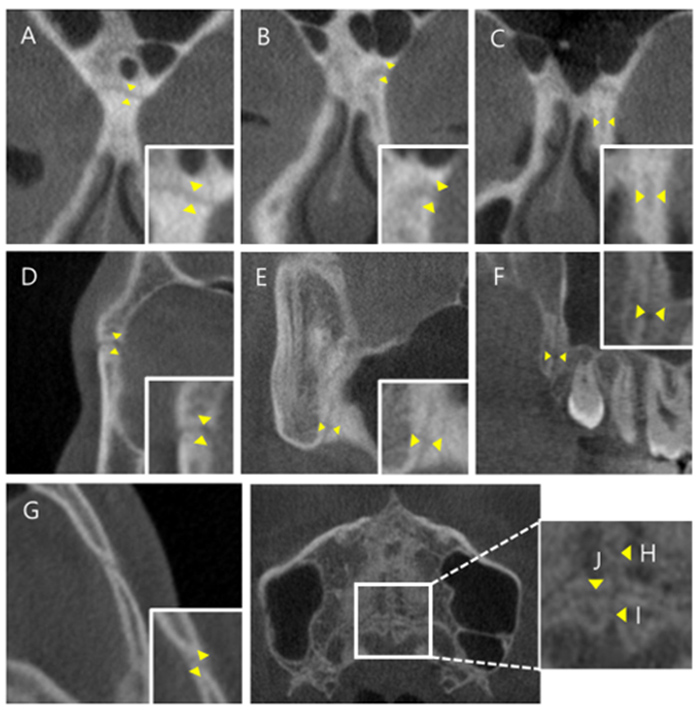

비수술 악궁확장 치료 MARPE (Miniscrew-assisted rapid palatal expansion)

Evaluation of miniscrew-assisted rapid palatal expansion success by comparing width of circummaxillary sutures before expansion in adult male patients” – Angle Orthodontics

논문 발췌 사진

이지민 원장은 성인 비발치 교정의 핵심인 비수술 악궁 확장 가능성을, 직접 연구한 논문 결과를 바탕으로 사전에 정밀 분석·예측합니다.

이 연구들은 현재 연세꿈꾸는치과의

교정 프로토콜에 적용되고 있습니다.